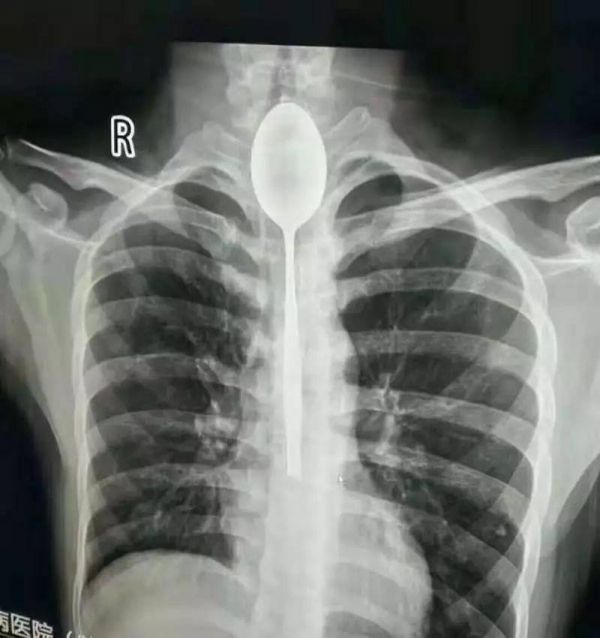

Доктора, обследовавшие пациента, который жаловался на боль в груди, были потрясены, обнаружив целую большую металлическую ложку, застрявшую в его пищеводе.

Сделав рентген и эндоскопию, во время которой в тело пациента вставили тонкую пластиковую трубку с прикрепленной камерой, врачи с удивлением обнаружили 20-сантиметровой столовый прибор.

«Я был потрясен. В моей практике никогда ничего подобного не случалось, — сказал доктор Юй Сиву. — Когда пациент поступил к нам, его пищевод уже загноился».